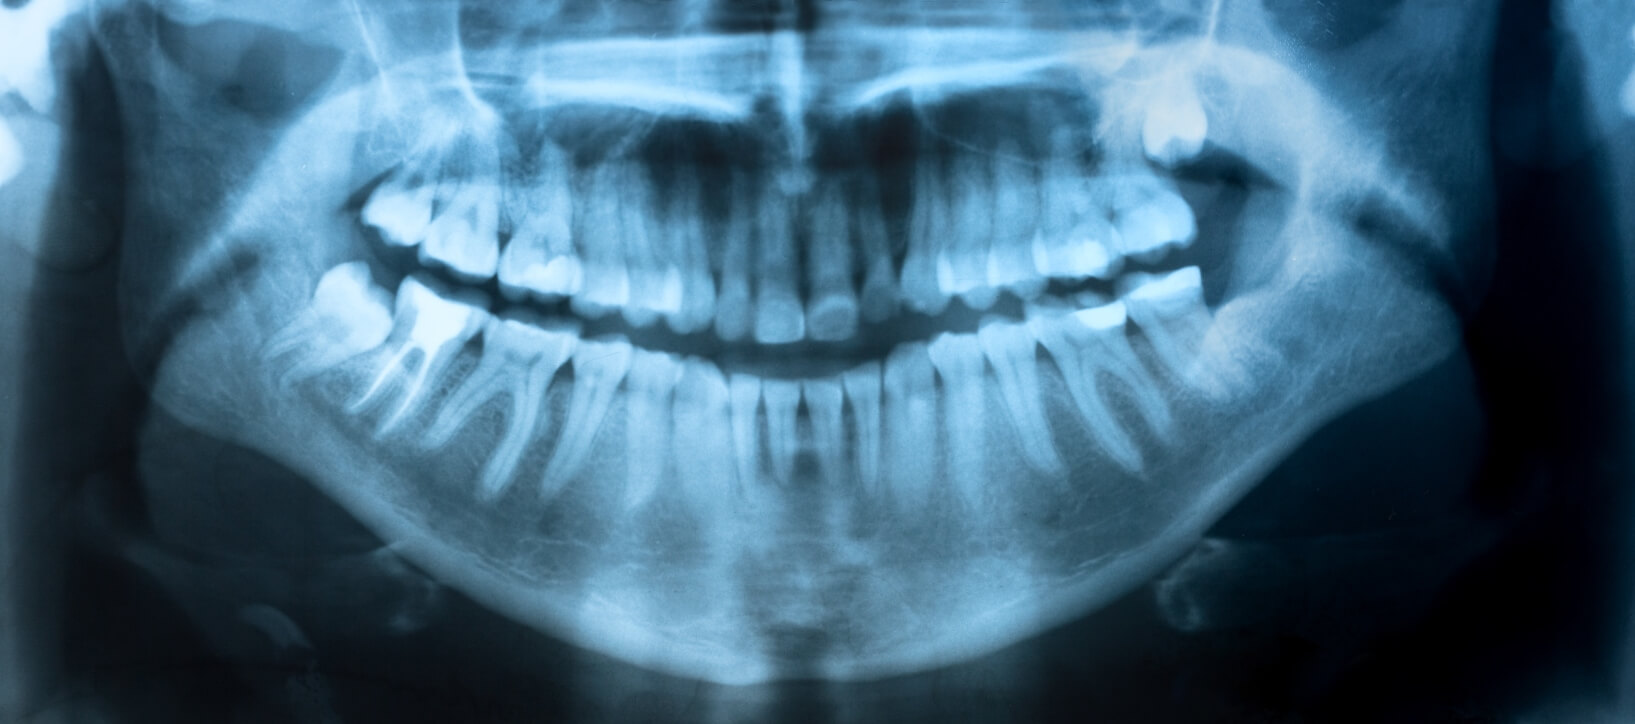

full mouth xray

How Eating Disorders Can Affect Oral Health

Eating disorders are very serious emotional and physical problems that can have life altering consequences, including damaging effects on your oral health.

Anorexia Nervosa, bulimia and binge eating are all eating disorders. While they differ in many ways - one thing they all have in common is they all include regurgitation—throwing up— as one of the symptom. When a person regurgitates, their stomach acid comes up and it is severely damaging to the teeth.

Oral Health Effects of Eating Disorders

The acid in the stomach is actually similar in strength to battery acid. Battery acid has a PH of 1, and stomach acid has a PH of 2. The lower the PH number, the higher the acidity. Stomach acid has the ability to destroy tooth enamel, and once it’s gone, it is gone forever. Tooth enamel does not grow back, so we need to do everything possible to protect it and keep it healthy.